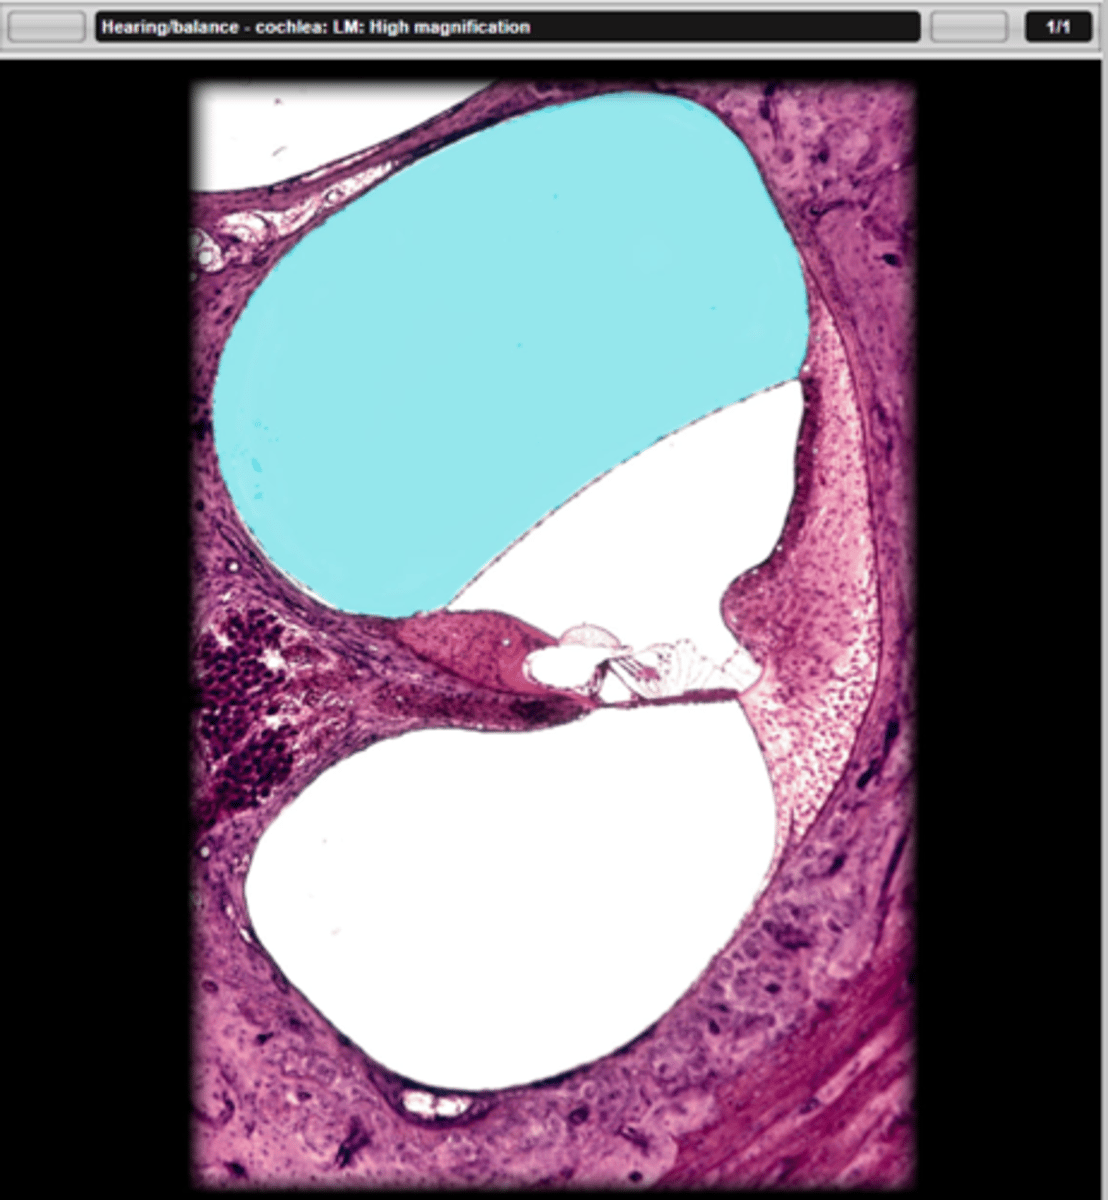

scala vestibuli

name the part in blue

scala tympani

cochlear duct